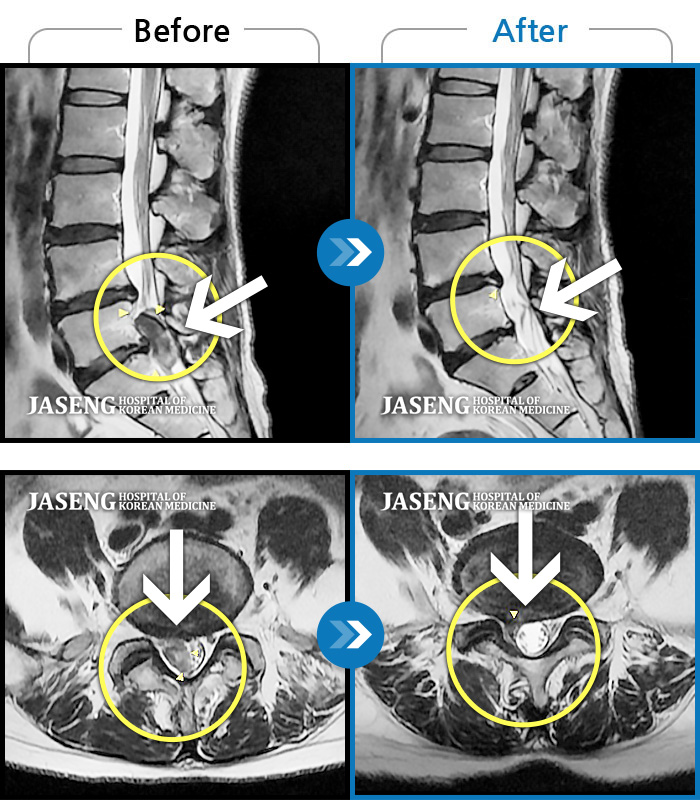

허리디스크

해운대 · 이상건 원장

허리통증, 좌측 다리 저림 및 근력 저하

촬영시기

2017.09.08 ~ 2018.05.11